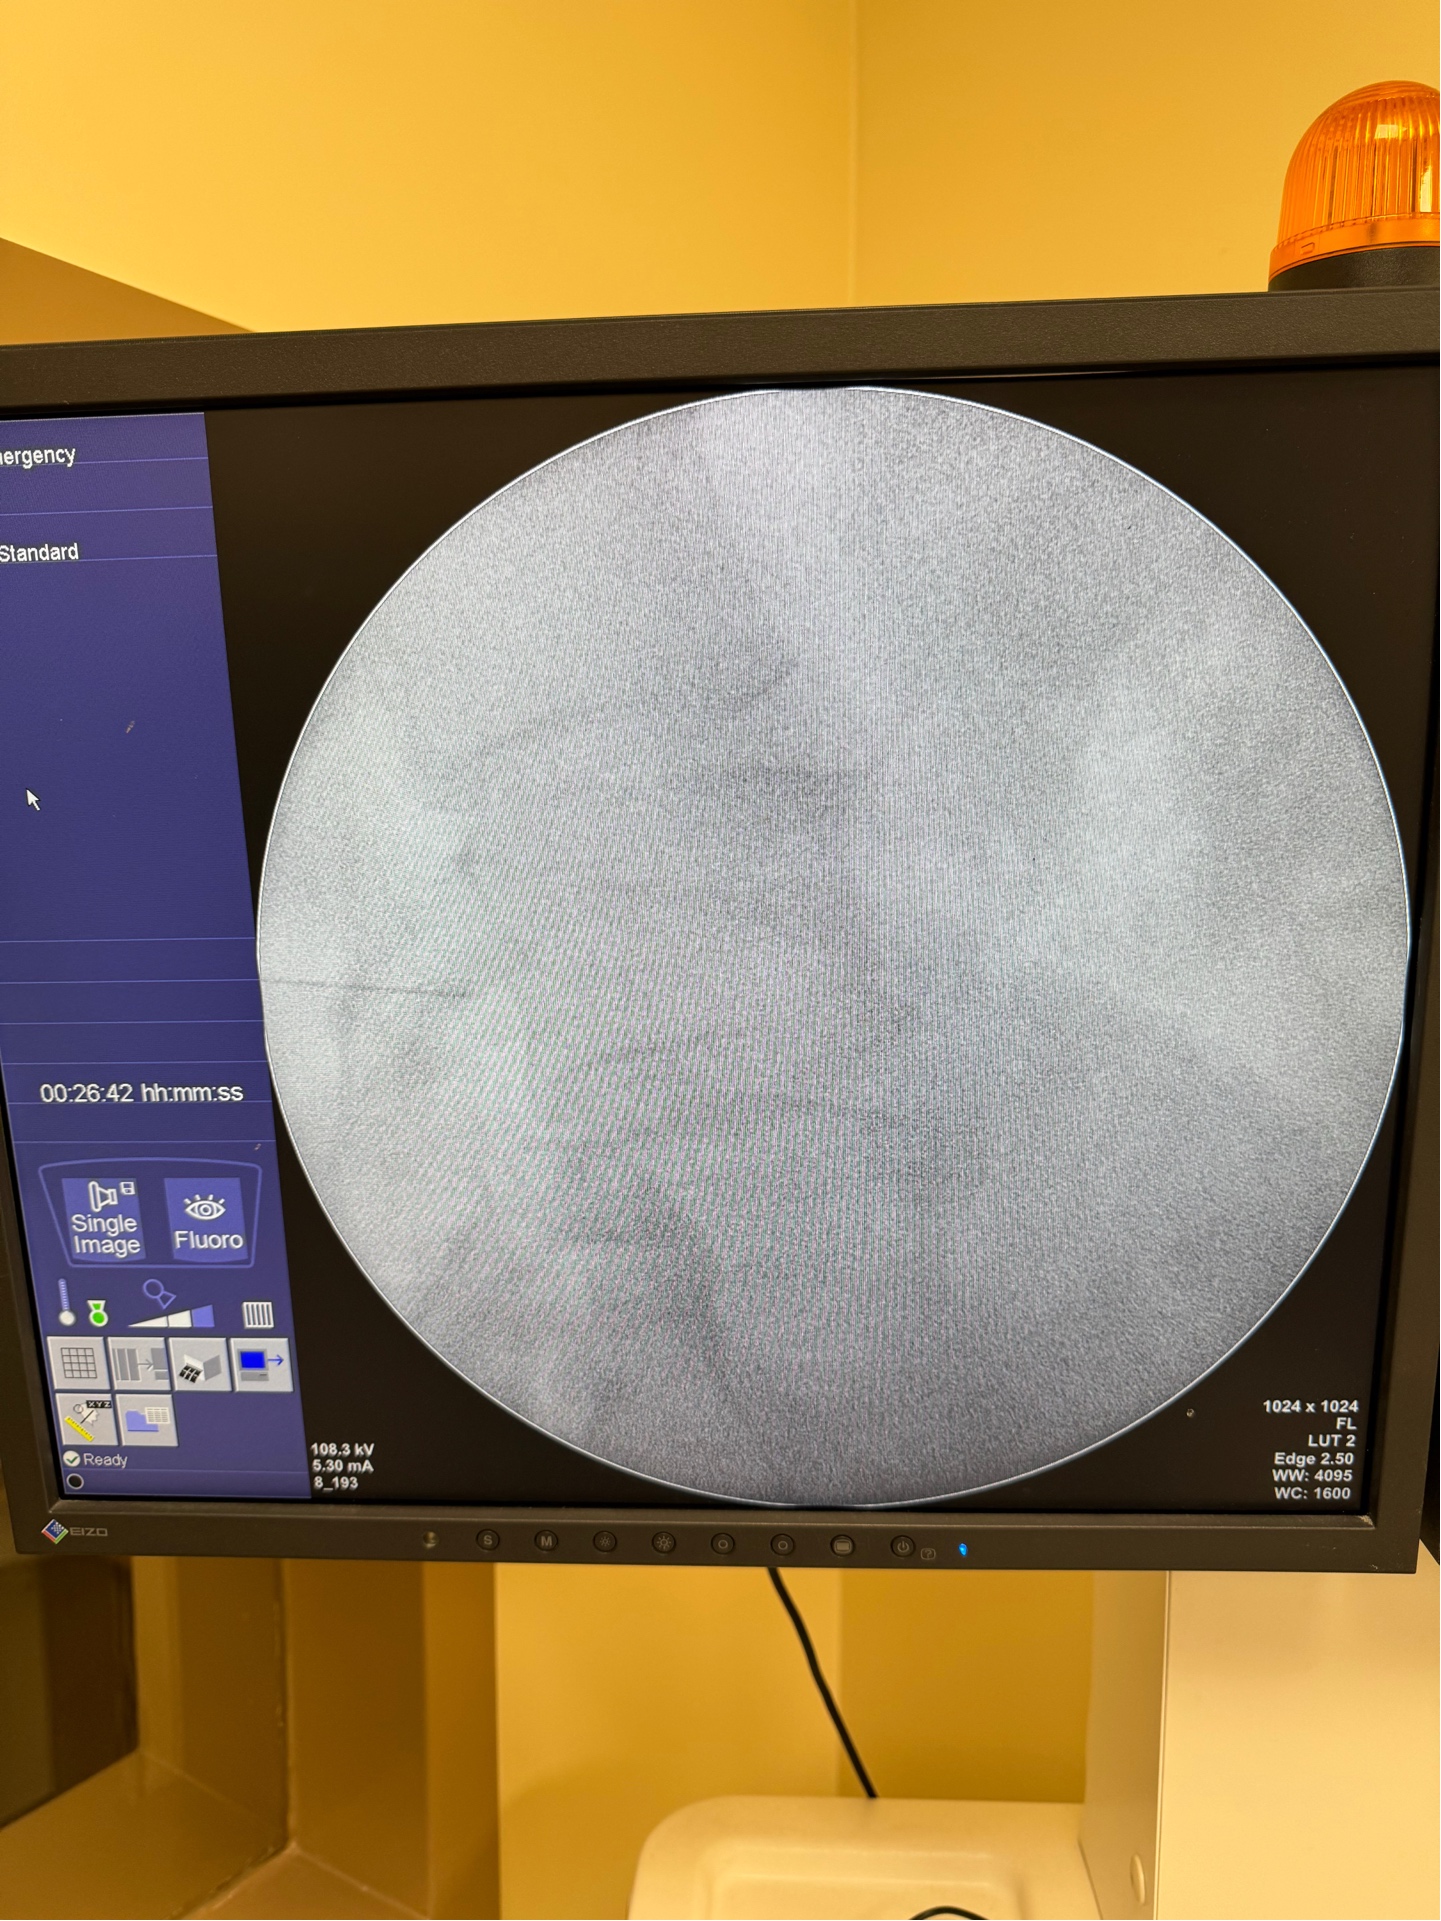

High-Precision Image-Guided Injections

All our injection procedures are performed under real-time imaging guidance using ultrasound and/or C-arm fluoroscopy. This advanced technology ensures maximum precision, optimal needle placement, and enhanced patient safety for superior treatment outcomes.